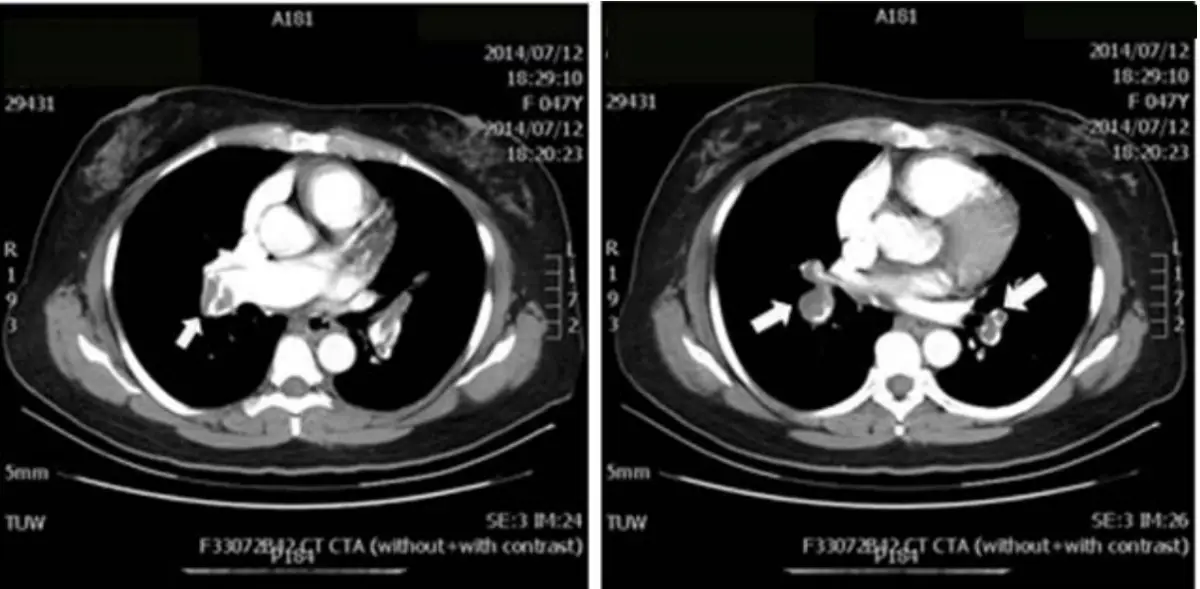

女性病人現年47歲,G2P2,主訴近來一個月間時有頭昏,並有漸進式呼吸困難。住院前四天症狀更形惡化,是乃經急診住加護病房。理學所見: 身高163cm; 體重 67.4kg; BMI = 25.37; 體溫:36.5℃ ;BP(mmHg): 128/60; PR(/min): 104; RR(/min): 24; 臉血蒼白; 心跳快速但正常律動, 在三尖瓣區有Grade 3/6 systolic murmur可聞 ,其他尚無重大異常。其心電圖及胸部X光和Computer tomography如圖。 D-Dimer, 3.56 mg/L;Blood gas:pH,7.534;PaO₂,57 mmHg;PaCO₂,20.9 mmHg;HCO₂ std 22.0 mmol/L;病人住院後隨即靜注大方劑量(Bolus dose) Unfractionated Heparin 3000u 及每小時1000u靜脈輸注。病程中先後進行下列處置: (1)通知心臟科啟動PCI團隊 (2) 查Protein C ,Protein S和anti-thrombin III, 和Anticardiolipin IgG (3)Tumor biomarkers :CEA, CA-199,CA-125,CA-153 (4)Heparin bolus 3000 unitIV stat and then IV pump 6~12 U/kg/hr according to the aPTT (5)Digoxin o.25 mg + 20% glucose in water for IV to control tachycardia 請問下列何組處置才是正確的?

本題考察肺栓塞(pulmonary embolism, PE)的診斷與處置。病人為47歲女性,表現為漸進性呼吸困難、頭暈、臉色蒼白、心搏過速(104次/分),三尖瓣區收縮期雜音(Grade 3/6),D-Dimer顯著升高(3.56 mg/L),血液氣體分析顯示呼吸性鹼中毒合併低氧血症(pH 7.534、 57 mmHg、 20.9 mmHg),高度符合急性肺栓塞表現。影像亦支持此診斷。本題核心在於辨別哪些處置是正確且必要的,哪些不適合或反而有害。

影像分析: